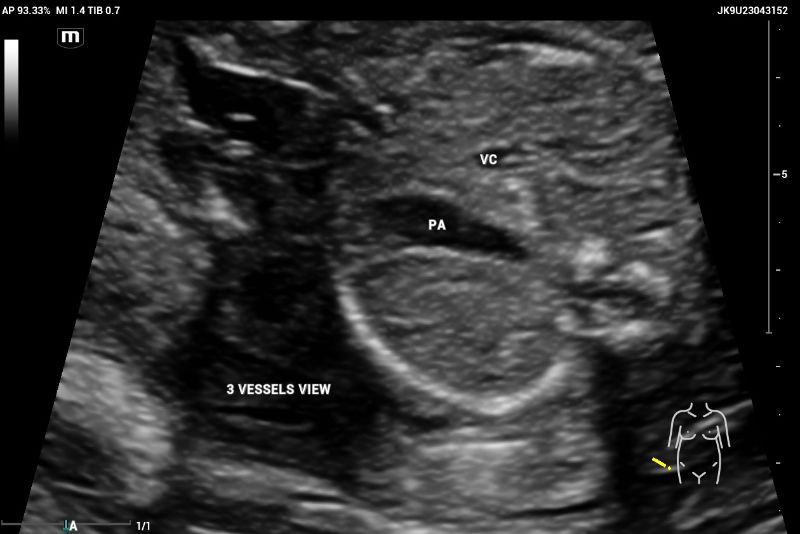

The ultrasound, performed on the Mindray Resona I9 system, showed an asymmetric four-chamber view. A single right ventricle was noted on the axial plane during the four-chamber view (4CV). The right ventricle appeared significantly larger than the left ventricle, with an absent left ventricular cavity. Only the main pulmonary artery (PA) and the vena cava could be identified on the three-vessel view (3VV)( Figures 7 and 8).

Axial image of thorax showing CASE with abnormal 3-vessel view demonstrates the absence of aorta between two vessels, the cava vein (CV) and pulmonary artery (PA), suggesting aortic atresia

Figure 8. Axial image of thorax showing CASE with abnormal 3 vessels view demonstrate the absence of aorta between two vessels the cava vein (CV) and pulmonary artery (PA) suggesting aortic atresia.